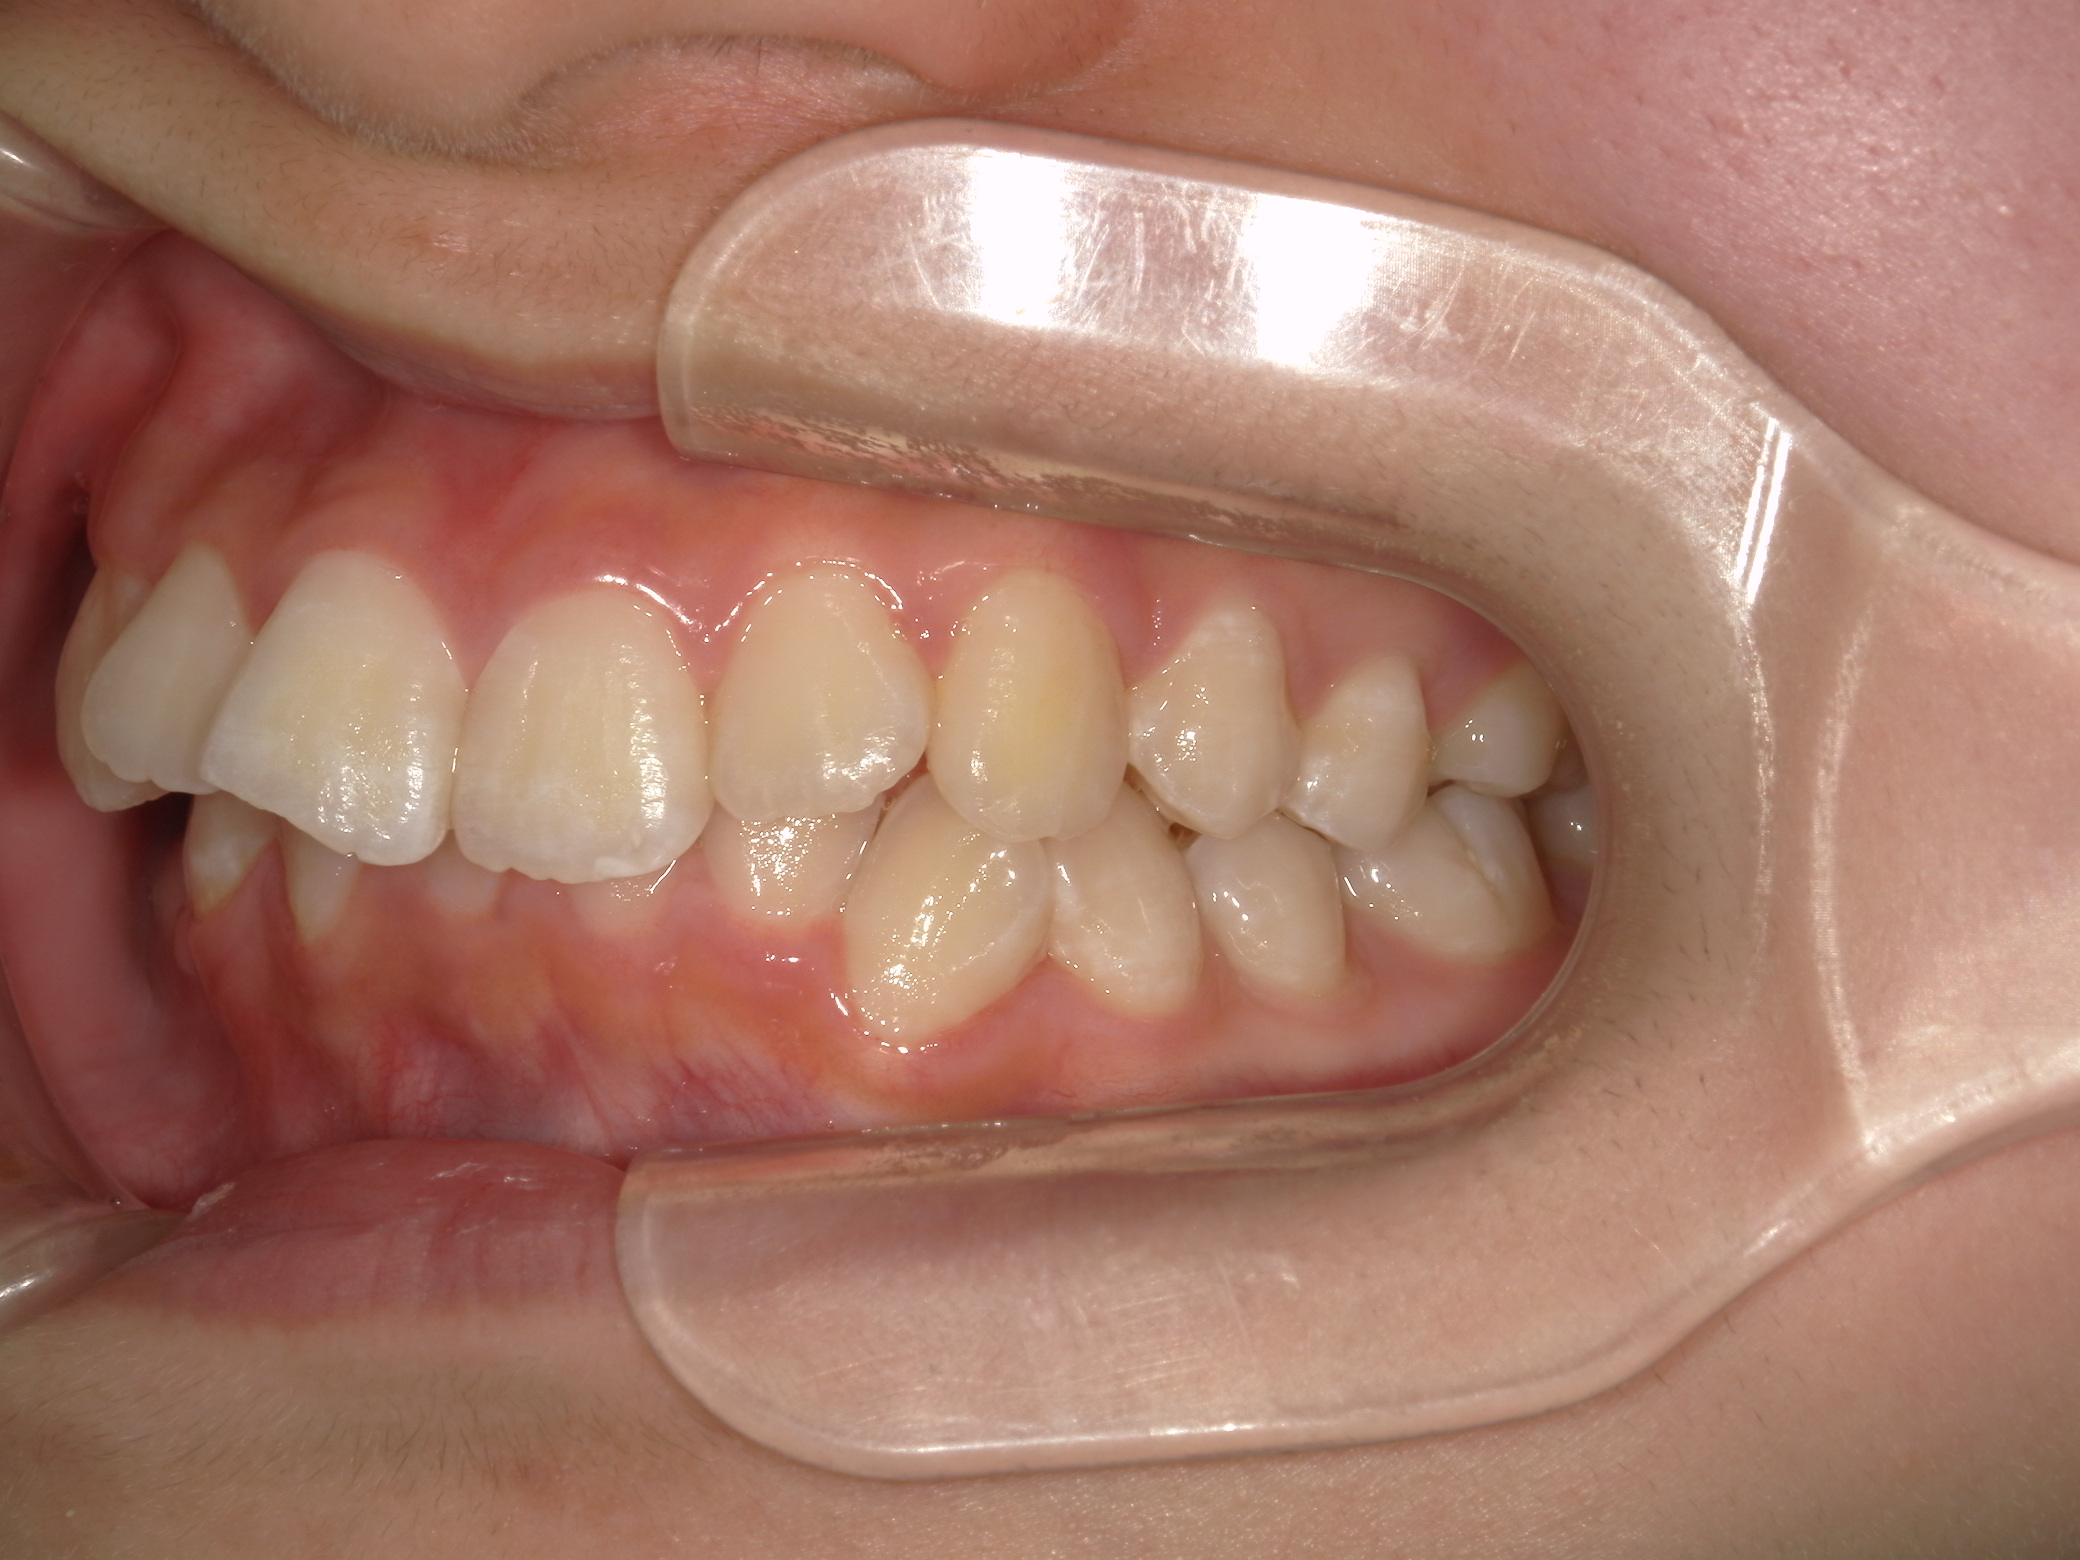

【中学生】インビザラインフル 上顎前突(出っ歯)と 叢生(でこぼこ) を改善

小学生で開始

インビザライン フル

でこぼこ

出っ歯

過蓋咬合

非抜歯

2期治療のみ

Before

After

治療期間

2年

治療開始

14歳

種類

インビザライン矯正

使用装置

インビザラインフル

コメント

先天欠損歯がある患者さんです。

途中 留学されたので 治療を進める速さを遅くした時期もありました。

しっかりはめてくれて 奥歯の咬み合わせも改善し治っています。